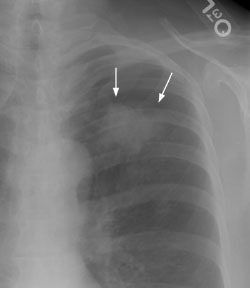

Example 2: This patient is an example of a false negative CT for hilar nodal metastases even when applying the suggested new criterion. The patient had a peripheral adenocarcinoma in the left upper lobe (black arrows). The left hilar node (yellow arrows) is not pathologic by size criteria, nor does it exhibit a convex margin with the adjacent lung parenchyma. This is a normal node by CT, however, at histopathologic analysis the node was positive for malignant cells.

NOTE: Click image to enlarge